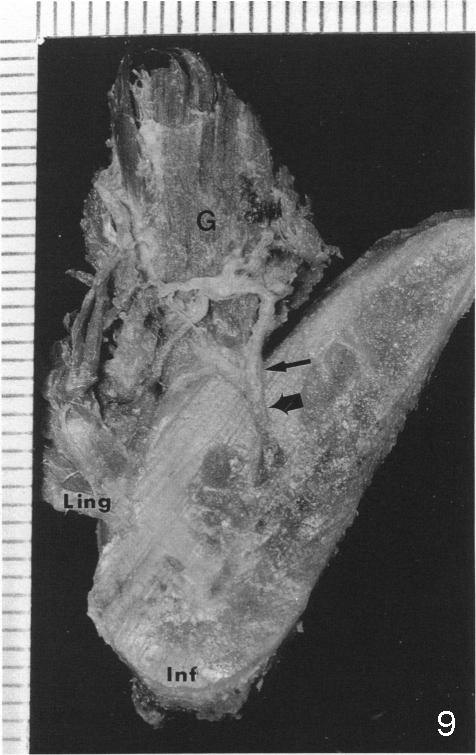

舌动脉(Lingual artery)是颈外动脉(External carotid artery)第二个前分支(图一),舌动脉末分支是舌下动脉(Sublingual artery)。舌动脉行于下颌骨舌侧(图二),它末分支舌下动脉中止于下颌骨切牙舌侧(图三),舌下动脉与颏下动脉(Submental artery,面动脉(Facial artery)分支)有吻合(箭头)。下颌骨舌侧有多个小孔(图四):正中(a, d),侧(c, e)舌孔,主要动脉穿入(1)。全景片(图五),前牙根尖片(图六)可显示舌孔(箭头, Lingual foramen)。舌孔延伸下颌骨舌侧一半(图七),下前牙植牙造成严重出血(图十,十一,2),往往是因为舌侧骨板穿孔,研究表明牙槽骨萎缩是血管意外(舌侧骨板容易破裂)主要因素(3,图八a,图九),预防方法:术前下颌骨舌侧触诊,对危险性大的病例做CT检查;术中钻洞时做下颌骨舌侧触诊,对危险性大的病例,翻瓣,暴露舌侧骨板,保护舌侧结构,使用短种植体。